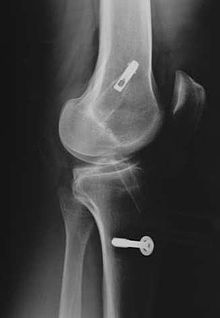

The patellar tendon connects the patella (kneecap) to the tibia (shin). The graft is normally taken from the injured knee, but in some circumstances, such as a second operation, the other knee may be used. The middle third of the tendon is used, with bone fragments removed on each end. The graft is then threaded through holes drilled in the tibia and femur, and screwed into place. It is slightly larger than a hamstring graft.